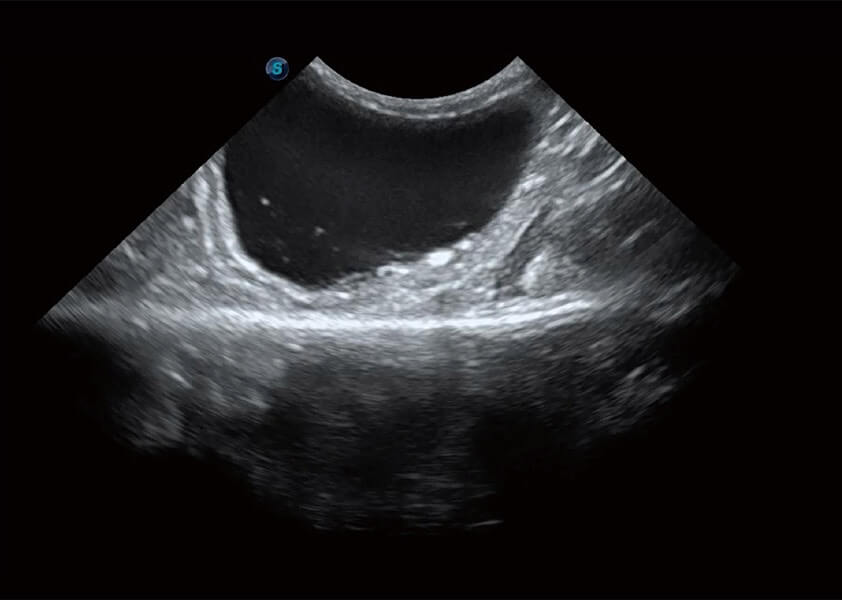

(犬)胆囊泥沙

(猫)膀胱结晶

(犬)肾脏血流